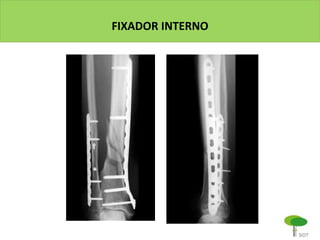

FIXADOR INTERNO

EXEMPLOS

MIPO no lado tibial

RAFI convencional no lado fibular